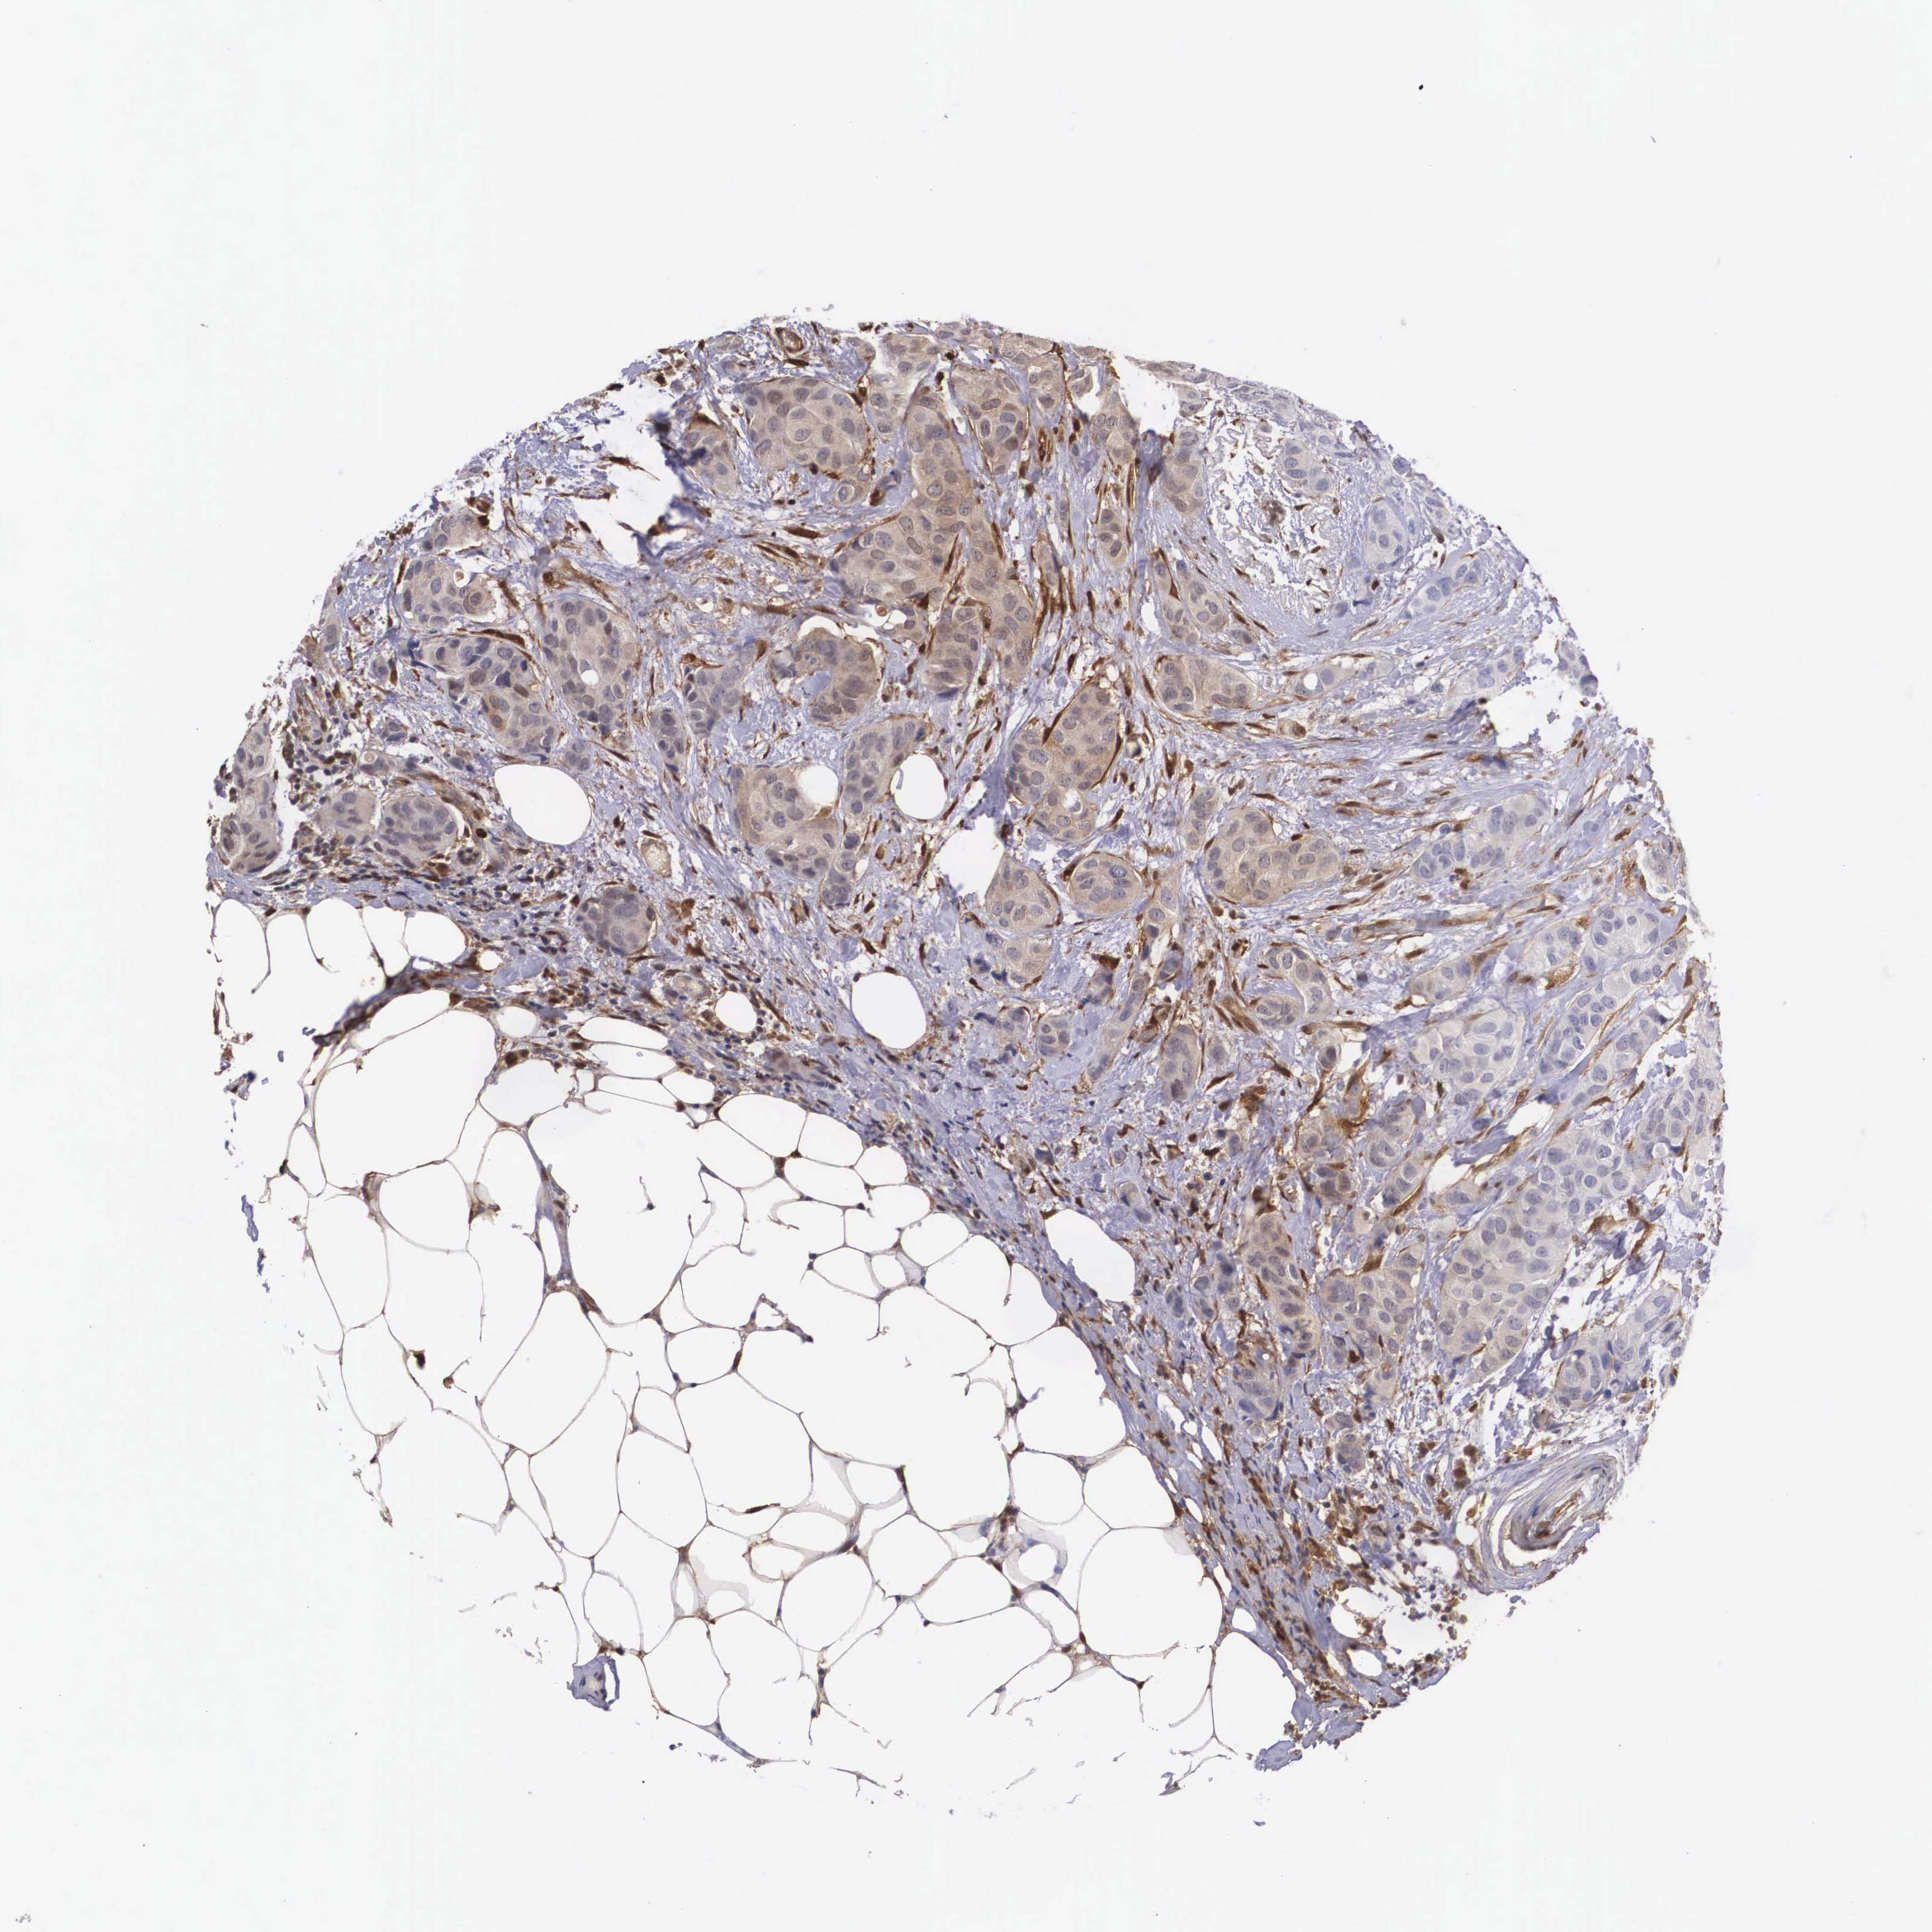

CANCER BREAST CANCER Show tissue menu

BRCA TCGA BRCA VALIDATION PROTEIN EXPRESSION